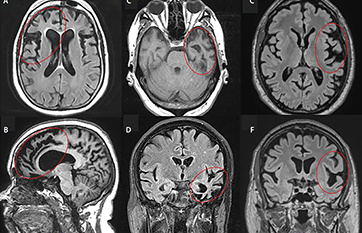

In the early stages people have one type of symptom language or behavior deficits which results in a subtype diagnosis. FTD involves degeneration of the frontal and temporal lobes of the brain. The average person lives four to eight years after receiving the diagnosis.

Frontotemporal Dementias Practical Neurology